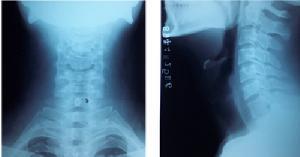

斜位拼音是xié wèi,是一种医学术语,投照方法为患者直立背向胸片架,使身体与暗盒成45°,中心线向头侧倾斜10~20°。